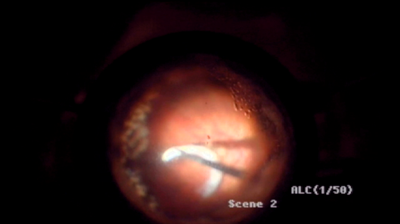

Figure 1: IOL (white arrow) removal with cutter and forceps trough a limbocorneal incision (a). Note the calcified Soemmerring’s ring that is separating at that moment (black arrow), falling back onto the retina (b), being eventually engaged with the fragmatome (c).

The case I presented told the story of a previously vitrectomised pseudophakic eye, in which the intraocular lens (IOL) was found to be dislocated into the vitreous cavity. The 23-year-old three-piece IOL was easy prey for removal with cutter and forceps through a limbo-corneal incision during a 23-gauge pars plana vitrectomy (Figure 1a). However, the remaining Soemmerring ring had calcified and decided not to come out with the IOL. Due to its irregular shape it could neither be removed easily with forceps (Figure 1b), nor destroyed by the cutter in the vitreous cavity. In the end, a 20-gauged fragmatome had to be used to fragment and remove the Soemmerring ring (Figure 1c).